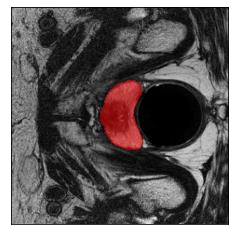

Machine learning models are typically deployed in a test setting that differs from the training setting, potentially leading to decreased model performance because of domain shift. If we could estimate the performance that a pre-trained model would achieve on data from a specific deployment setting, for example a certain clinic, we could judge whether the model could safely be deployed or if its performance degrades unacceptably on the specific data. Existing approaches estimate this based on the confidence of predictions made on unlabeled test data from the deployment's domain. We find existing methods struggle with data that present class imbalance, because the methods used to calibrate confidence do not account for bias induced by class imbalance, consequently failing to estimate class-wise accuracy. Here, we introduce class-wise calibration within the framework of performance estimation for imbalanced datasets. Specifically, we derive class-specific modifications of state-of-the-art confidence-based model evaluation methods including temperature scaling (TS), difference of confidences (DoC), and average thresholded confidence (ATC). We also extend the methods to estimate Dice similarity coefficient (DSC) in image segmentation. We conduct experiments on four tasks and find the proposed modifications consistently improve the estimation accuracy for imbalanced datasets. Our methods improve accuracy estimation by 18\% in classification under natural domain shifts, and double the estimation accuracy on segmentation tasks, when compared with prior methods.